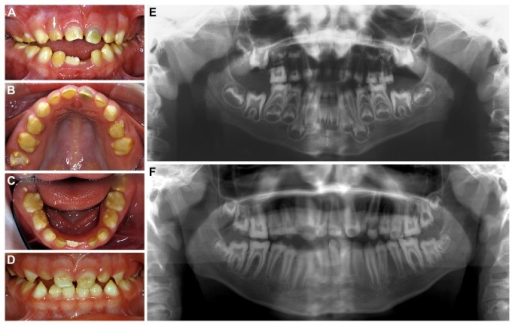

El síndrome de Jalili se caracteriza por la asociación de amelogénesis imperfecta (AI; ver este término) y distrofia de conos y bastones (CRDs; ver este término). Fue descrita únicamente en una familia con 29 individuos afectados. AI es un término genérico que designa un grupo de enfermedades hereditarias de los dientes que tienen en común anomalías del esmalte dental. El esmalte dental puede ser fino pero normal, o hipomineralizado, o los dos. CRDs es un trastorno de la retina raro que provoca inicialmente: pérdida de la visión central, defectos en la visión de los colores y fotofobia antes de los 10 años de edad; y posteriormente: ceguera nocturna y disminución del campo de visión.

Jalili syndrome is characterized by the association of amelogenesis imperfecta (AI; see this term) and cone-rod retinal dystrophy (CORD; see this term). It has been described in only one family with 29 affected individuals. AI is a generic term for an inherited group of dental diseases in which the common clinical feature is an abnormality of tooth enamel. The enamel may be thin but normal, and/or hypomineralized. CORD is a rare retinal disorder that leads to an initial loss of central vision, color vision and photophobia before the age of 10 years with subsequent night blindness and visual field restriction.